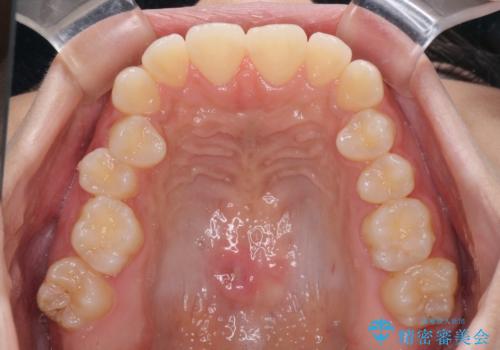

- 上下のデコボコと奥歯の咬みにくさを気にして来院された患者様です。

上顎骨の幅が下顎骨よりも小さく受け口傾向であったため、拡大装置により上顎骨の骨幅を広げて上下関係を改善し、その後インビザラインにて歯並びを整えることとしました。

下顎歯列は上顎歯列内に収まるように並んでいますが、上顎骨の幅が狭いと、下顎臼歯が全体的に舌側に傾斜した歯列となってしまいます。

舌側に傾斜した歯列は奥歯に力の負担がかかりやすく、歯磨きがしにくいなどの問題があるため、上顎骨拡大により舌側傾斜を改善することが可能となります。